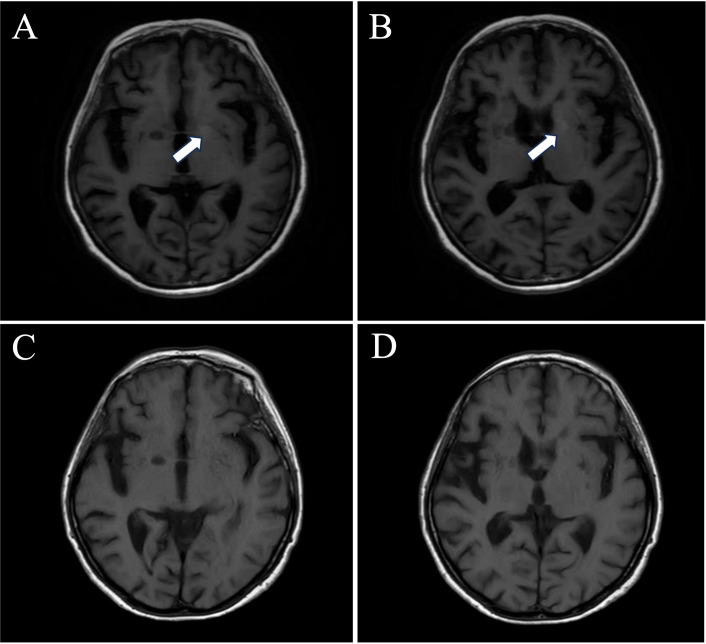

Results: All four patients exhibited signs of limbic encephalitis, including short-term memory deficits, seizures and psychiatric disturbances. Two cases also presented with faciobrachial dystonic seizures. MRI findings revealed hyperintense basal ganglia lesions in two patients. Treatment with corticosteroids, intravenous immunoglobulin and mycophenolate mofetil led to significant improvement in three patients, with no relapses during a follow-up period ranging from 33 to 60 months. One patient succumbed to pneumonia despite initial improvement of neurological function.